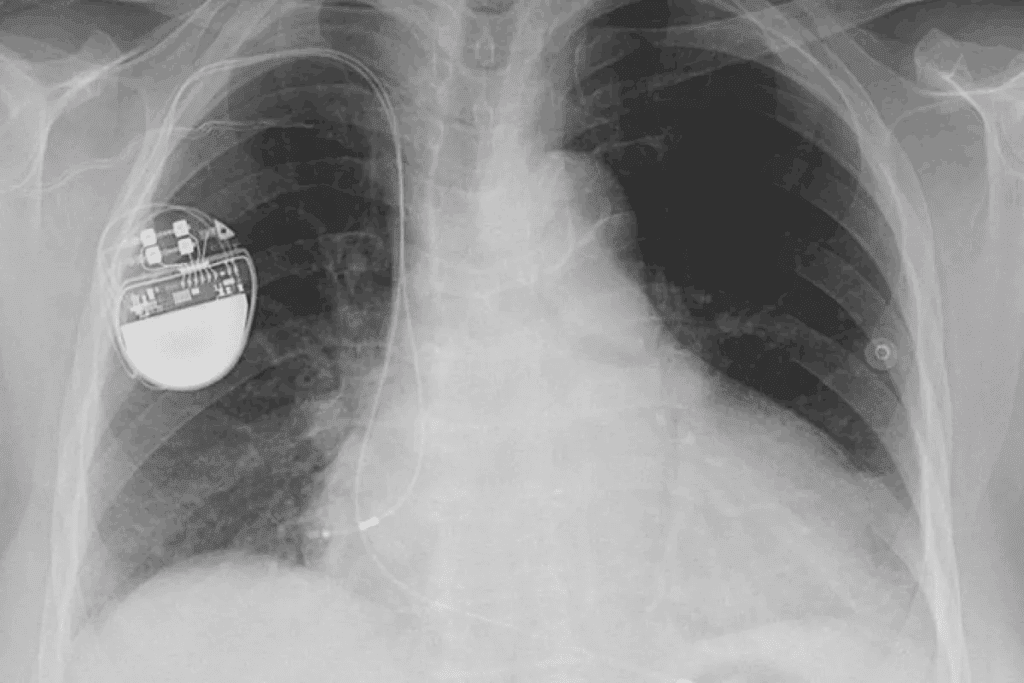

The Basics of Cardiac Pacemakers

Understanding pacemakers is key for managing heart conditions like AFib. A pacemaker is a small, battery-powered device. It prevents the heart from beating too slowly. The Medical organization says pacemakers keep the heart’s rhythm regular.

How Pacemakers Function

Pacemakers send electrical impulses to the heart. This makes it beat at a regular rate. They are programmed to fit the patient’s needs, adjusting the heart rate based on activity.

The Implantation Procedure and Recovery

The implantation procedure involves a small incision in the chest. The pacemaker is placed under the skin. Leads are guided through a vein into the heart. Recovery usually includes a short hospital stay for monitoring.